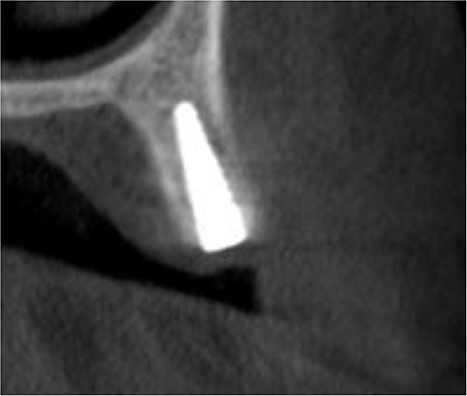

Under local anesthesia with 4% articaine solution, a full-thickness flap was raised to expose the alveolar ridge. The initial point was marked with a point drill. The implant site was first prepared with a 2.2 mm pilot drill, and then with a 3.3 mm drill. After preparing the implant bed, we noticed the disappearance of the coronal and middle third of the buccal wall, exactly as planned. A submerged implant system (INNO submerged implant; Cowellmedi Inc, South Korea) was inserted according to the manufacturer’s instructions (Fig. 1). The insertion torque value was 33 N.cm. several perforations were prepared at the buccal side of the recipient bone bed using a small round bur for better blood supply. An allogeneic bone graft material (Cortical Cancellous powder; TRCIR Co, Iran) was used to reconstruct the buccal plate. A prefabricated L-shaped titanium mesh has been adapted to fit the shape of the alveolar ridge to be reconstructed, and it was fixed to the implant with a cover screw (Fig. 2). The flap was mobilized to permit a tension-free primary closure, was closed with 4–0 silk sutures. Sutures removal was done after 1 week. The surgical sites were left to heal for 6 months.

Inserting a dental implant of 3.5 mm diameter and 10 mm length into its prepared bed. The implant was completely surrounded by bone in its apical third only.